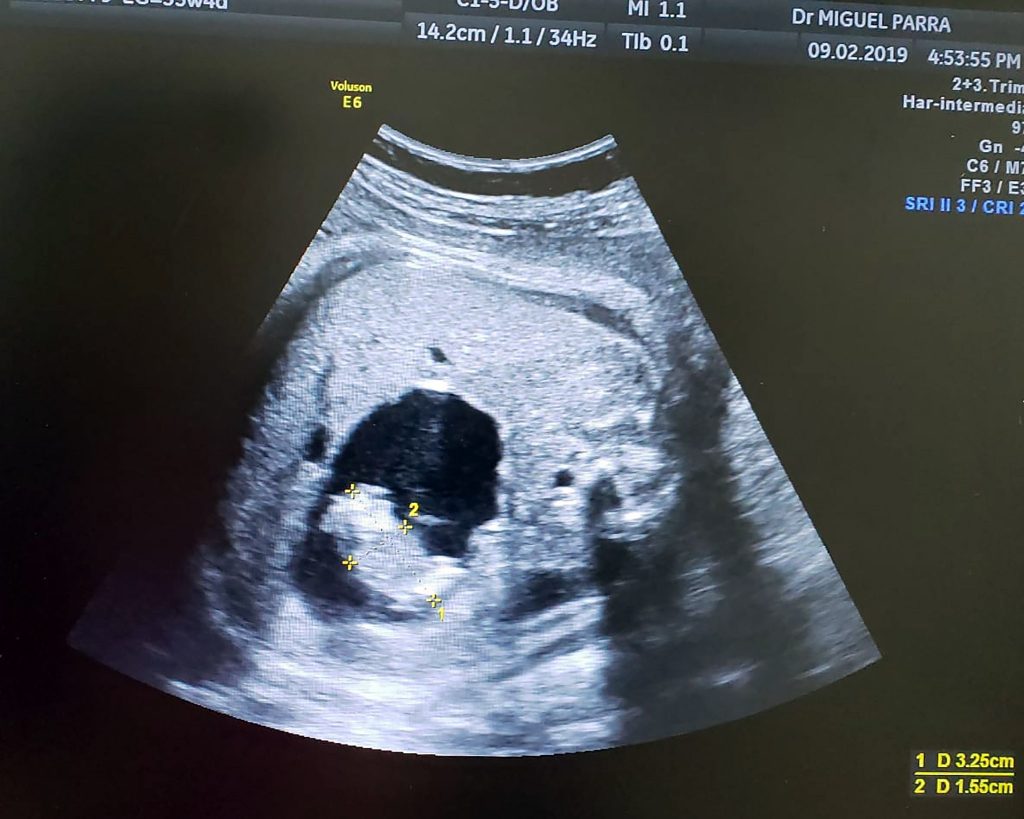

Un'ecografia mostra un piccolo feto che si forma nell'addome della sorella gemella mentre si trova nell'utero. Credit: Miguel Parra-Saavedra

Ma attraverso una ecografia particolare, il dottor Parra-Saavedra è stato in grado di vedere che lo spazio pieno di liquido conteneva effettivamente un bambino minuscolo, con tanto di cordone ombelicale separato che che si collegava all’intestino della gemella più grande.